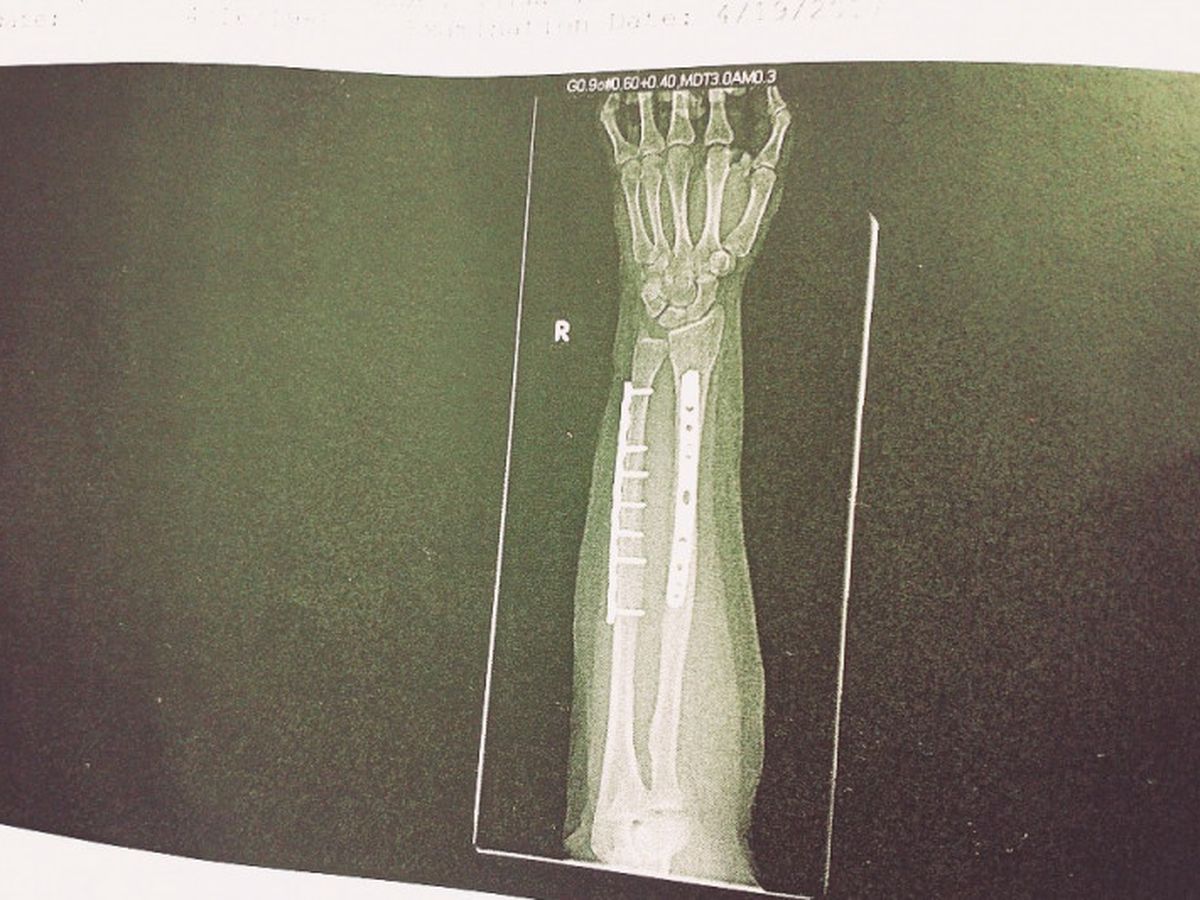

Hey guys, if you know me you probably know the deal already: On April 18th, I fell down the stairs outside my apartment and broke my right arm, both the radial and ulnar bones, in a compound fracture

(that’s when the bone goes out of the skin).

A guy and his dog and two ladies found me screaming on the sidewalk and called an ambulance. I was taken to the emergency room. I was in Harborview hospital for several days, had surgery to set the two broken bones. As you can see, I have some cool metal additions to the inside of my arm now and two really intense scars.